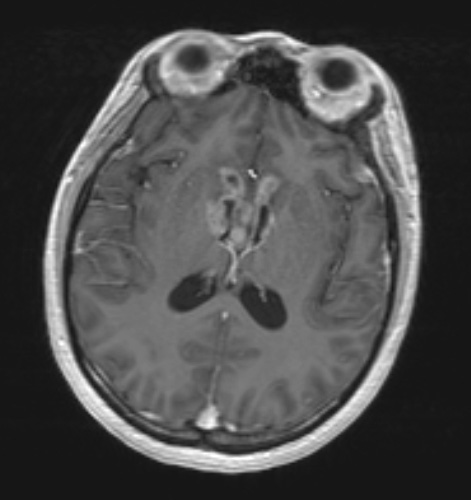

17A3,4 Ventricular spread as shown in a T1-weighted image with contrast (17A3) and T2-weighted (17A4) scans.